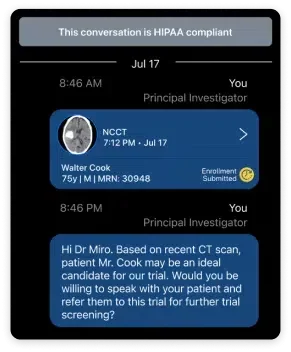

Viz Recruit Patient Recruitment Software expedite clinical trial enrollment for partners and contract research organisations. This is our AI-powered solution that identifies eligible clinical trial candidates, connects the research team, and accelerates clinical trial enrollment (CTE)––all in a secure, compliant environment.

- Notifies clinical and research team of new discoveries

- Mobile and desktop alerts are sent to the research team

- 100% of Viz RECRUIT alerts are viewed by research teams, with 50% read within the first 10 minutes

- HIPAA compliant, so you can communicate and coordinate across your network